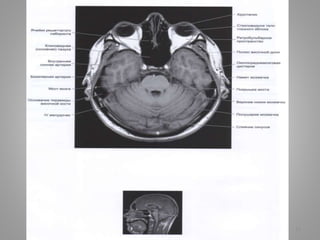

МРТ хворого із нормотензивною

гідроцефалією (сполучною)

• Рис. А. Аксіальний зріз у Т2-режимі. Рис. В. Фронтальний зріз.

• Шлуночки непропорційно збільшені відносно субарахноїдального

простору.

• Зображення недостатньо чіткі внаслідок рухів хворого: такі пацієнти

часто унаслідок асоційованої деменції неспроможні лежати нерухомо

під час сканування.